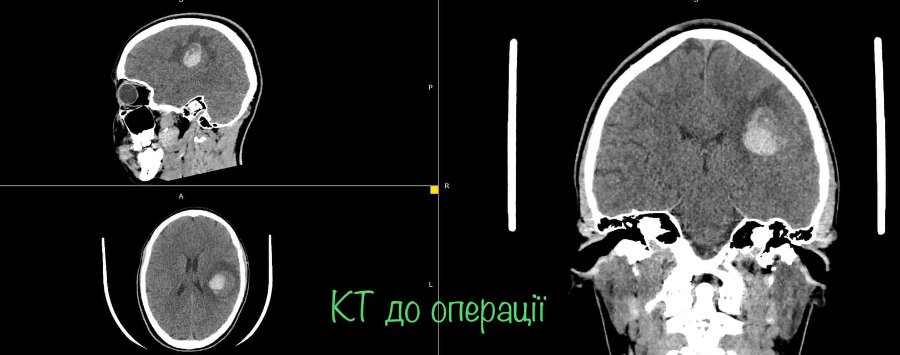

На МРТ виявили пухлину головного мозку з крововиливом в лівій домінуючій (важливішій) півкулі, в якій, власне, окрім центрів, які рухають кінцівками однієї половини тіла, розташований дуже важливий центр мови.